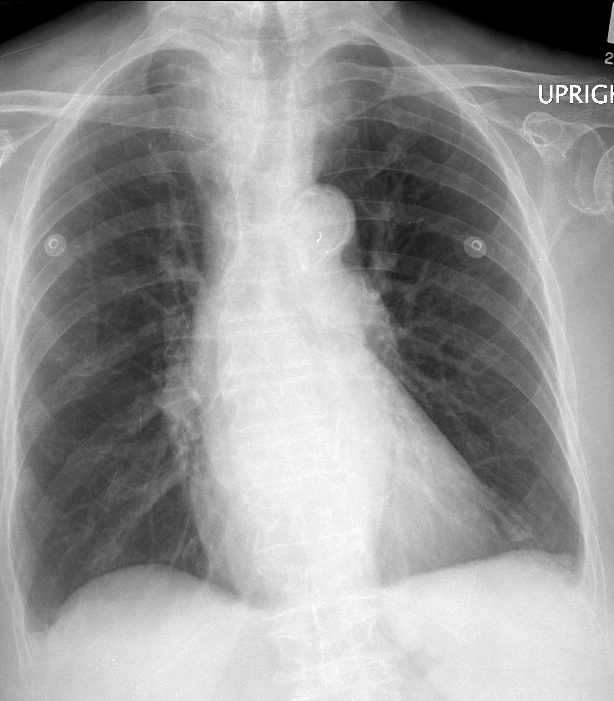

Thyroid Mass

Case 2 PA